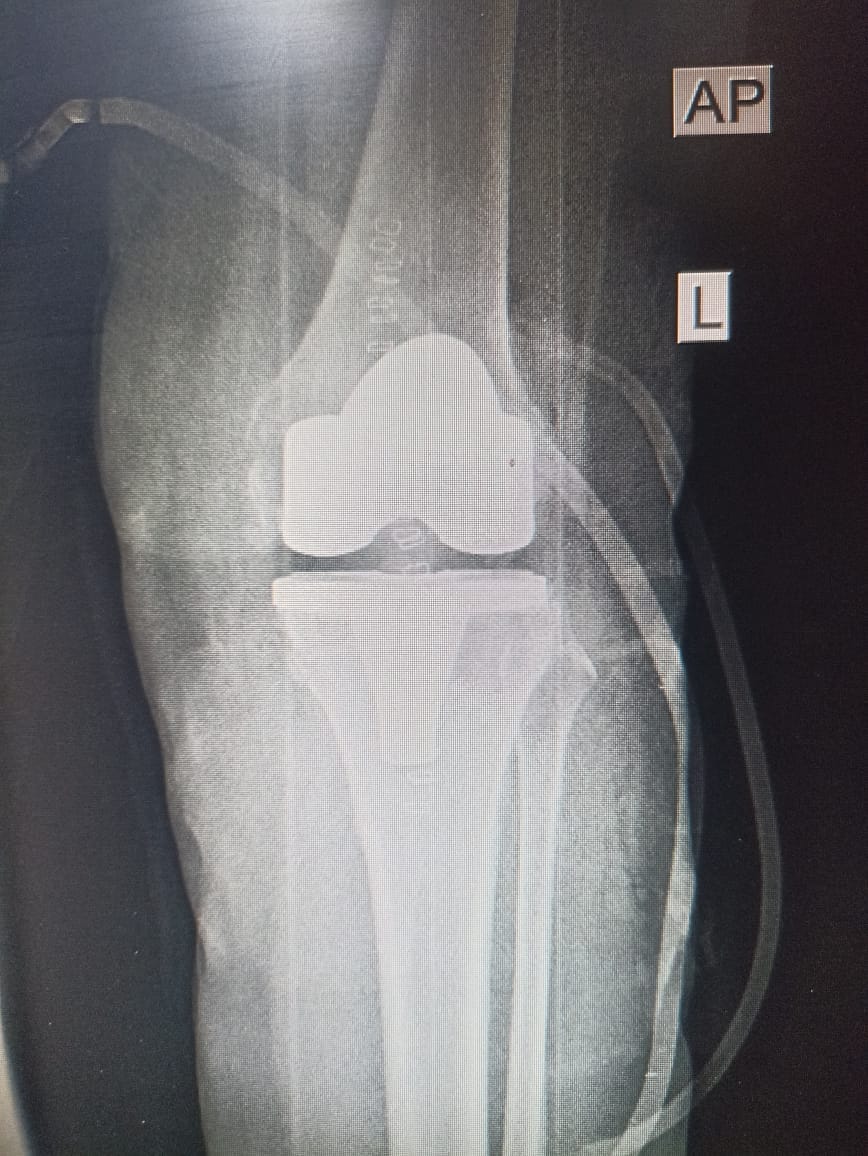

فريق طبي جراحي في مستشفى ابن سينا يجري عملية نوعية معقدة لمريضة تعاني من سوفان شديد في الركبه .

اجرى فريق طبي جراحي في مركز ابن سينا التخصصي لجراحة العظام والكسور و تبديل المفاصل عملية تبديل مفصل...

فريق طبي جراحي في مستشفى ابن سينا يجري عملية نوعية لمريضة تعاني من سوفان شديد في الركبه .